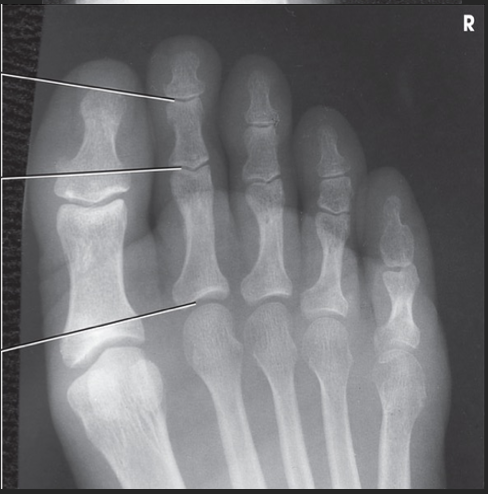

Name this projection.

AP oblique foot

Describe the position of the patient.

Seated or supine with their knee flexed and lower leg/foot rotated medially 30 degrees

Where does the CR enter?

Base of the 3rd metatarsal

What is demonstrated?

The lateral side of the foot from the toes to heel, the sinus tarsi, and the tuberosity of 5th metatarsal

The ________ metatarsals should be free of superimposition.

3rd-5th

Which metatarsals should be superimposed?

1st and 2nd

What could be done to demonstrate the opposite aspect of the foot?

Rotate the foot out laterally 30 degrees